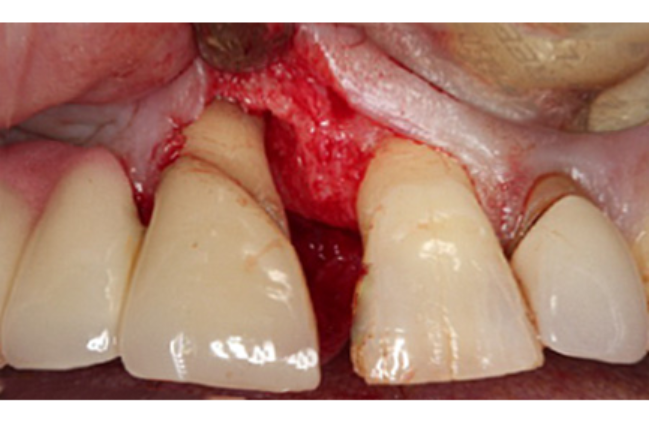

Periodontal surgery provides improved access to the roots and bone hidden under the inflamed gum. The gum is carefully peeled back to allow thorough decontamination of the root surface. Depending on the pattern of bone loss, a decision may be taken to re-contour the bone; which would allow the gum to heal in a more predictable manner.

In certain situations, there may be an opportunity to regenerate the lost bone. Bone grafting materials and special tissue stimulating proteins can be used to aid the re-growth of natural bone and improve the overall support for the tooth.